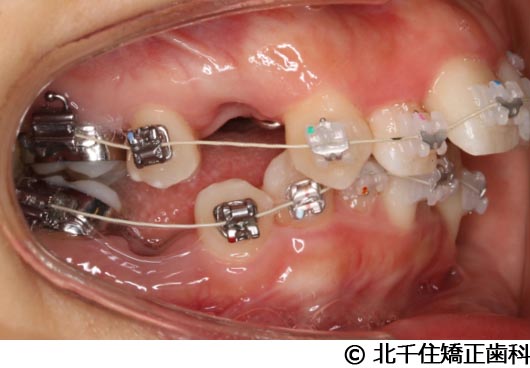

【症例5】上顎前突

- 治療前

- 治療後

- 治療名

- 上顎前突

- 費用

- 1,263,600円(税込)

- 期間

- 2年8ヵ月

- 治療回数

- 32回

- 通院頻度

- 1ヵ月ごと

- 年齢

- 13歳3ヵ月(初診時)

治療内容

-

患者様の症状

主訴:出っ歯

治療方法

骨格性の上顎前突、ヘッドギアを併用して上下顎第一小臼歯4本抜歯してワイヤー矯正。

治療結果

骨格性上顎前突に対し、ヘッドギアおよび抜歯を併用した矯正治療により歯列および咬合関係の調整を行った症例である。

治療後は保定装置を使用し、歯列および咬合の安定維持を目的として定期的な経過観察を行っている。